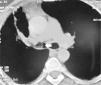

Case reportA 48-year old lady presented to the Chest Clinic with complaints of dry cough of six months duration. There was no history of fever, dyspnea, chest pain, wheeze or hemoptysis. She denied any addictions. Physical examination was unremarkable. Pulse oximetric saturation was 99% on room air. A chest radiograph was suggestive of volume loss in the right hemithorax (Fig. 1). Computed tomography (CT) of the thorax showed a low attenuation tumor in the right main bronchus suggestive of a fat containing lesion (Fig. 2). FB revealed the presence of a yellowish tumor with a smooth external surface causing near total occlusion of the right main bronchus (Fig. 3). The right upper lobe bronchus was not visualized and the bronchoscope could not be advanced into the right main bronchus. The patient was advised to have a rigid bronchoscopic removal of the tumor however she was not willing to have a general anesthesia.

DiscussionBenign endobronchial tumors present with clinical symptoms depending on the type of tumor (for e.g. most patients with carcinoid manifest with hemoptysis), extent of endobronchial obstruction, and the degree of distal parenchymal damage due to the obstruction.6,7 Lipomas constitute 3.2-9.5% of all benign endobronchial tumors.1 Nearly three-quarters of the patients are symptomatic and almost 80% have demonstrable chest radiographic abnormalities.6 The CT findings of the presence of a lesion with an attenuation of fat (−100 HU) and absence of enhancement following contrast administration is usually diagnostic of lipoma.4 Histologically, endobronchial lipomas are described by their primary mesenchymal component as hamartomatous, fibromatous, chondromatous, lipomatous, or leiomyomatous.8 The index case fits into the lipomatous variety. Squamous metaplasia may be seen in the overlying epithelium, as in the index case.9